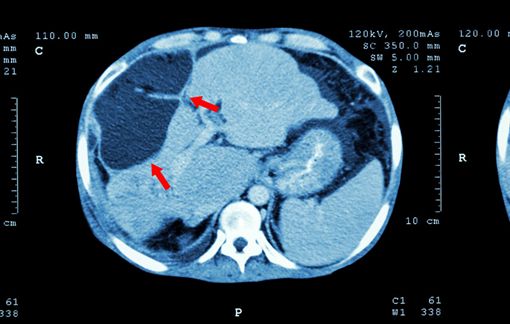

然而 , 最近一段时间 , 两人出现了 腹泻 , 腹胀等情况 , 同时腹部疼痛也加重了许多 , 就到医院进行了检查 , 没想到竟然查出了肝癌 。

幸运的是癌细胞还没有扩散 , 当夫妻两人知道这样的结果以后 , 感觉天都要塌了 , 两个人相互抱头痛哭 。